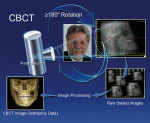

CBCT scanners use a 2D detector (Figure 1), which allows for a single rotation of the x-ray source-detector system to generate a scan of the entire region of interest, as compared with conventional CT scanners, where multiple ”slices” must be stacked to obtain a complete image.

All CBCT units provide 3D information; however, each manufacturer approaches the project differently with its choice of patient positioning, scanning parameters, and viewing software. CBCT units most commonly are categorized by their x-ray detection system:18 image-intensifier (II) detector or flat-panel (FP) detector.19 II detectors are an older and less expensive technology, which generally results in more noise than FP detectors, and they need to be preprocessed to reduce geometric distortions inherent in the detector configuration.20 The radiation beam is 3D in shape and similar to the photon energy used in digital or conventional dental radiology. The receptor captures 2D images either directly with the FP, which absorbs the photons that are converted to an electric charge which is measured by the computer, or with the II, which captures the photons and converts them to electrons that contact a fluorescent screen that emits light captured by a charged-coupled device (CCD) camera. The software then reconstructs the sum of exposures with the manufacturer’s proprietary algorithms into as many as 512 axial slice images.21